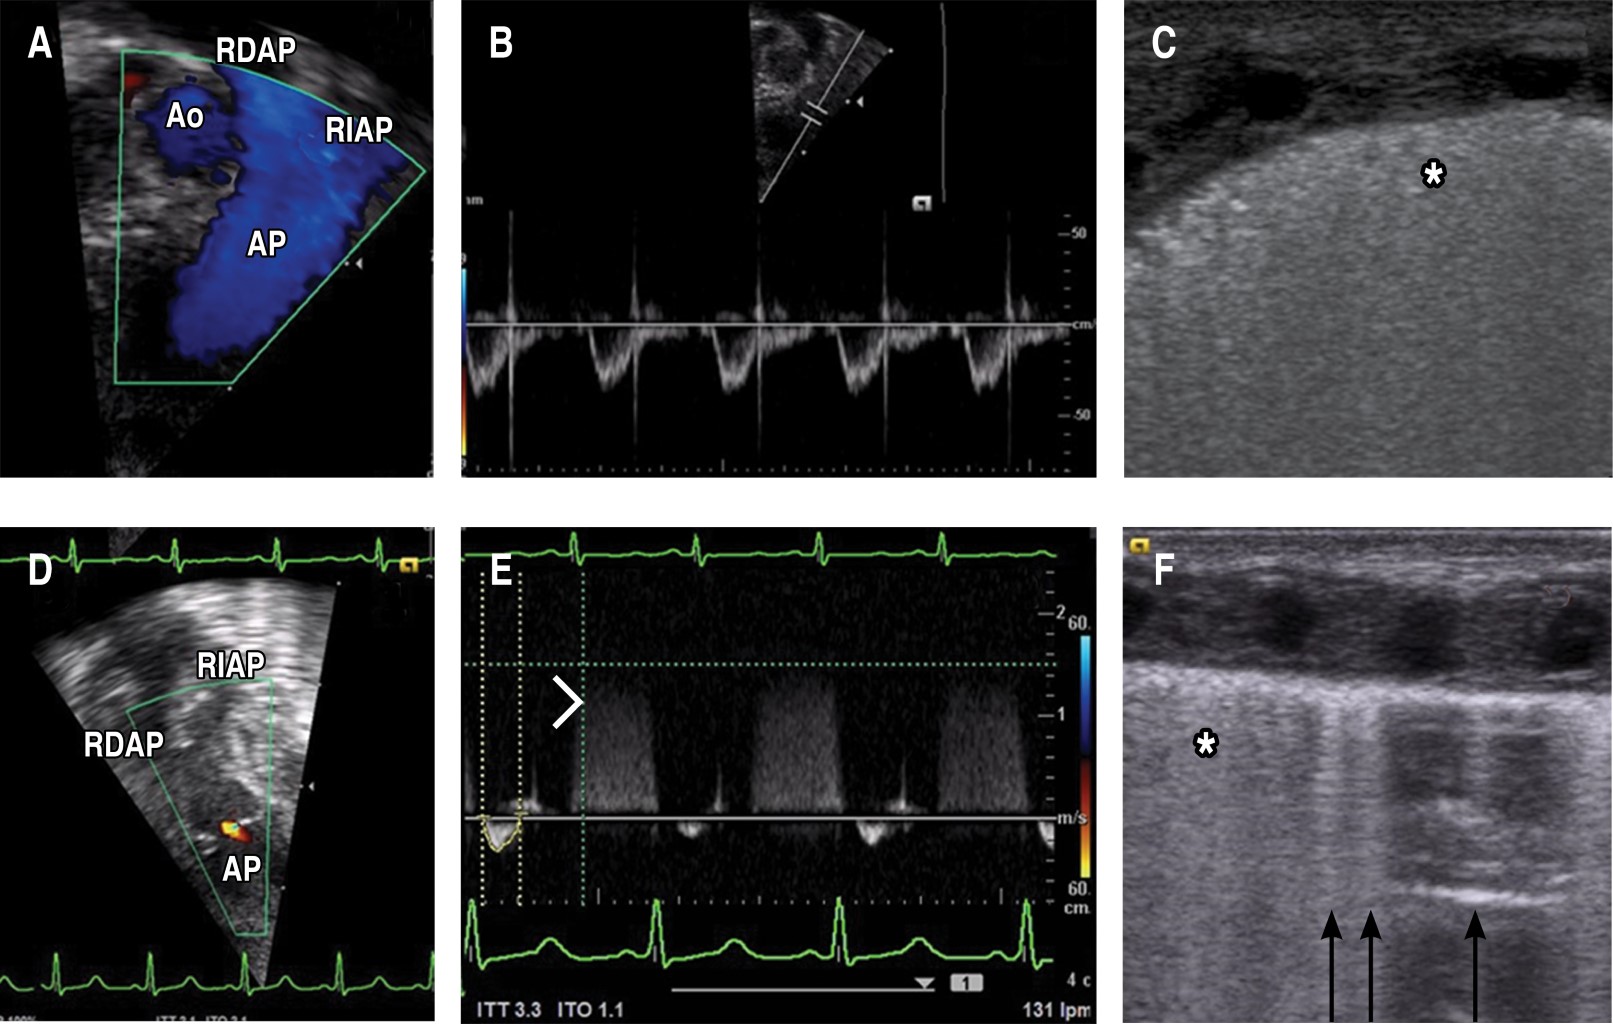

El paciente llegó a la UCIN con un catéter arterial y canalizado en una vía periférica; como parte de los cuidados se procedió a "ajustar" el catéter arterial, y además se colocó un catéter umbilical venoso. Minutos después del procedimiento presentó deterioro hemodinámico súbito, insuficiencia respiratoria hipoxémica (FiO2 100%) e incremento de lactato (de 5 a 17 mmol/L), por lo que a las 12 horas de vida se realiza nueva evaluación por USG cardiaco, observando disfunción biventricular grave, presencia de imagen hiperecogénica con sombra acústica en "cola de cometa" en el tracto de salida del ventrículo derecho (TSVD), lo cual generaba obstrucción (Figura 2 A); predominio del cortocircuito de derecha a izquierda a través del CAP de 2.6 mm sin encontrar datos de tamponade. En el USG pulmonar se descartó neumotórax y derrame pleural (Tabla 1 y Figura 1 D-F).

Se incrementó la dosis de epinefrina, se inició hidrocortisona y se agregó vasopresina. Se dio manejo con hemoderivados por descenso de la hemoglobina a 8 g/dL. Momentos después, el servicio de cardiología corrobora la imagen hiperecogénica, la cual desapareció dos horas después, y ya sin detectar el gradiente obstructivo.

Nuestro caso presentó deterioro súbito de la función cardiaca, lo cual seguramente estuvo relacionado a EA que ocurrió posterior o durante la colocación de un acceso vascular, pero estando con ventilación asistida con presiones altas. El EA se considera una complicación grave; en la serie más grande, en la época antes del uso de surfactante se reportaron 25 casos con sólo un sobreviviente, proponiendo que las dos principales vías de entrada son la rotura de alveolos que genera paso de aire a los capilares y el uso de catéteres umbilicales.11 La presentación clínica más frecuente es el colapso hemodinámico repentino o datos de hipertensión arterial pulmonar grave, manifestándose como insuficiencia respiratoria hipoxémica. En el presente caso no se detectó neumotórax en el ultrasonido, ya que había deslizamiento pleural y líneas B (Figura 1 F) y en la placa de tórax sin datos de fuga aérea (Figura 2 B), por lo cual la entrada de aire parece corresponder a la colocación de catéter umbilical.

El EA puede afectar el corazón debido a que el aire tiende a migrar al TSVD, que es la parte más superior del corazón cuando se está en posición supina, alojándose cerca de la válvula pulmonar (Figura 2 C), causando diversos grados de obstrucción (lo cual se ha descrito como cerradura de aire, o air lock). En casos graves puede presentarse como una atresia pulmonar funcional (Figura 1 D).12 Esto genera un compromiso súbito, por choque hipovolémico dado al cese del retorno venoso pulmonar al corazón izquierdo, además de hipoxemia grave (en nuestro caso, agravada por la anemia), todo esto lleva a un resultado fatal.13

En nuestro paciente se detectó una imagen en "cola de cometa" mediante el USG, lo cual ocurre por un fenómeno de reverberación llamado artefacto anular descendente (ring-down artifact). Esto sucede debido a múltiples ecos que regresan al transductor, ya que el haz de ultrasonido reverbera de ida y vuelta entre las burbujas aéreas. Las burbujas se encuentran en líquido (sangre), por lo que hay muy poca atenuación y la secuencia de ecos que regresan al transductor permanecen intensos a través del tiempo (Figura 2 A).14